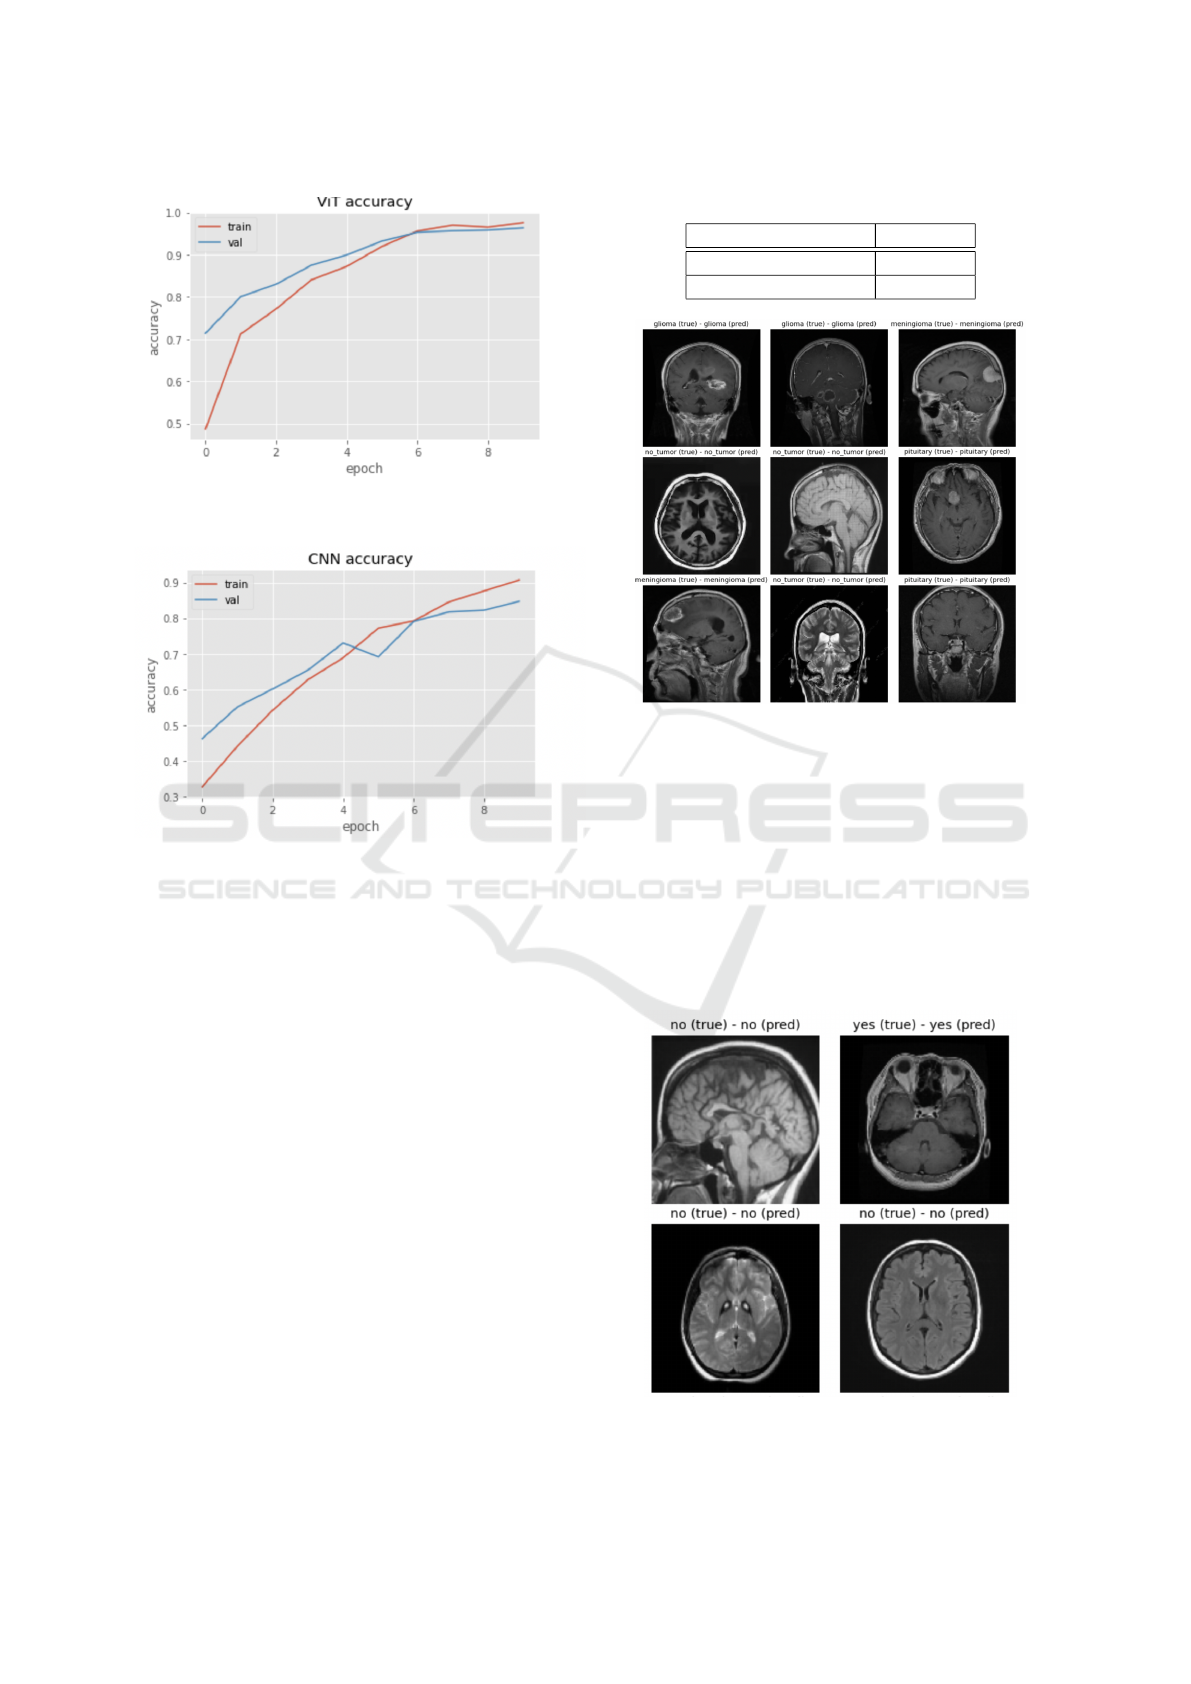

Table 3: Vision Transformer Confusion matrix for the Bi-

nary Model (Tumor/No tumor).

Tumor Detection no tumor tumor

no tumor 99 7

tumor 2 497

our custom-built CNN trained under the same exact

conditions. Although the model did not train on a

huge amount of data, and used an unbalanced it still

managed to achieve 96.5 % classification accuracy,

and over 98 % detection accuracy, which is impres-

sive. We compared to CNNs, which are used in the

SoA for such tasks, and demonstrated that the ViT

can still achieve better accuracy, despite lacking trans-

lational invariance. Some modifications could im-